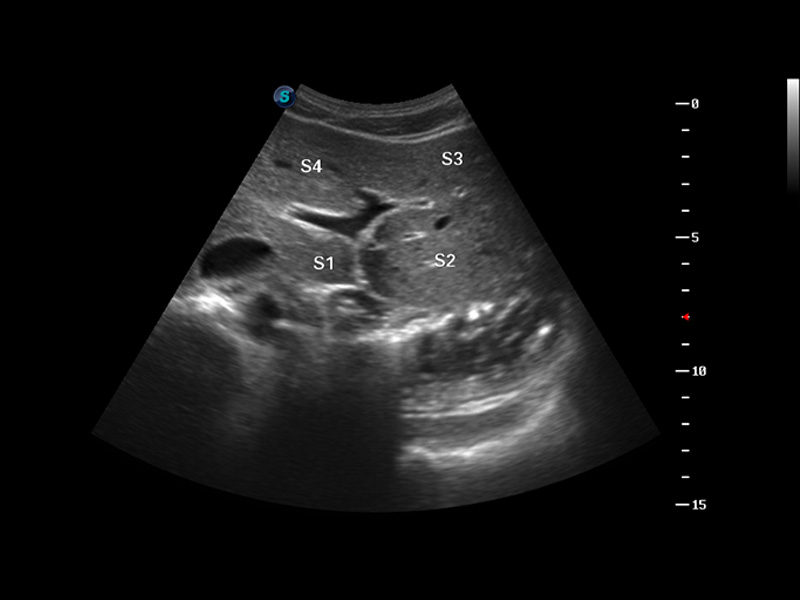

S8 EXP便携式彩色多普勒超声诊断仪是milan米兰研发的高端全身应用型便携彩超。高通道的VIS平台融合可视化(Visual)、智能化(Intelligent)和人性化(Smart)的特点,配以milan米兰自主研发生产的探头大家族,使您能够快速、准确的获得病人信息,提高工作效率的同时减轻疲劳。

μ-Scan微米成像

谐波成像

实时宽景成像

3D/4D成像